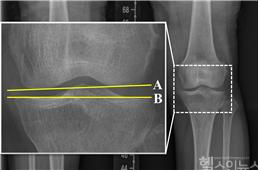

연구팀은 수술 전후 X-ray 사진을 통해 관절선 수렴각(JLCA), 무게중심선 비율(WBLR), 관절선 경사각(Joint Line Obliquity Angle) 등 다양한 방사선학 지표를 분석했다.

특히, JLCA가 과대 교정된 경우(내측 관절선 열림이 큰 상태, ΔJLCA가 5.6°보다 큰 경우)에는 수술하지 않은 반대쪽 무릎에서 관절염이 더 빠르게 진행되고 수술이 필요할 가능성이 높았다(P = .027, P = .006). 반대로, JLCA가 과소 교정된 경우(내측 관절선 열림이 작은 상태, ΔJLCA가 1.7°보다 작은 경우)에는 수술한 무릎에서 관절염이 더 심해지고, 인공관절 치환술로 전환할 가능성이 높았다(P = .014, P = .027).

이러한 결과는 수술 후 관절선 수렴각의 적정 교정을 유지하는 것이 무릎 건강을 장기적으로 보존하는 데 필수적이라는 것을 시사한다.